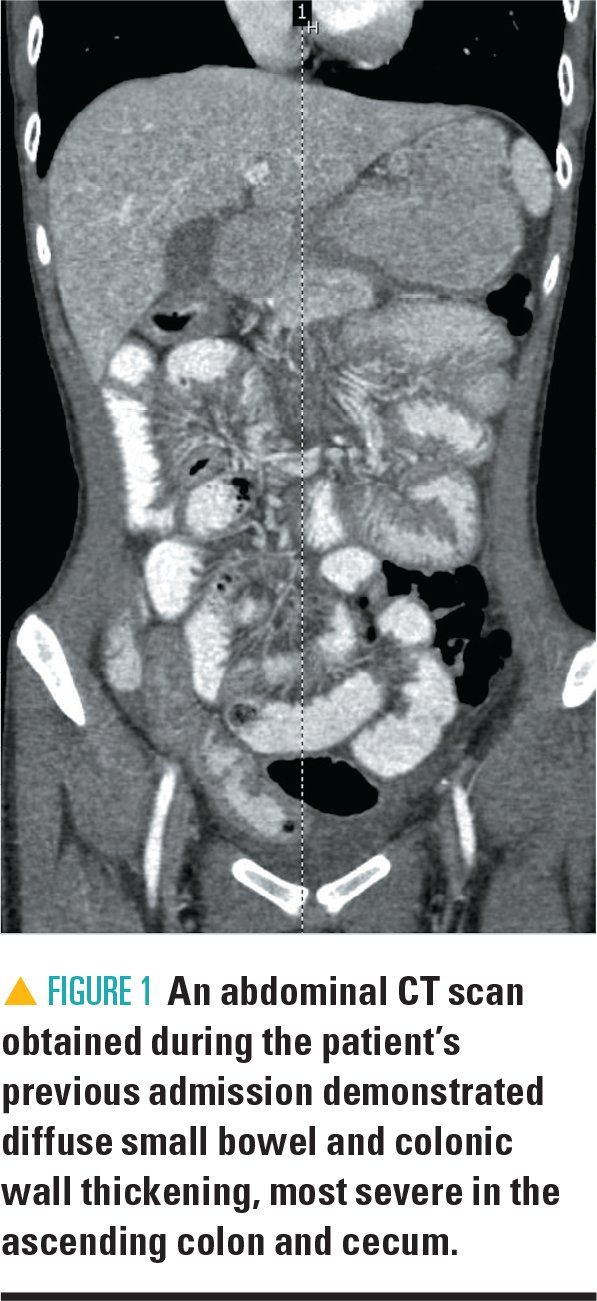

The patient’s physical examination is significant for mild, diffuse abdominal tenderness and absence of rebound or guarding. On further review, his weight has decreased from the 60th percentile to less than the 1st percentile over 2 years. His complete blood count shows a leukocytosis of 18.61 with an eosinophilia of 46% (absolute eosinophil count of 8640). His erythrocyte sedimentation rate and C-reactive protein are normal. Computed tomography (CT) scan of the abdomen is performed and shows diffuse small bowel and colonic wall thickening, most severe in the cecum and ascending colon (Figure 1). He is subsequently admitted to the inpatient pediatric ward for further workup and management.